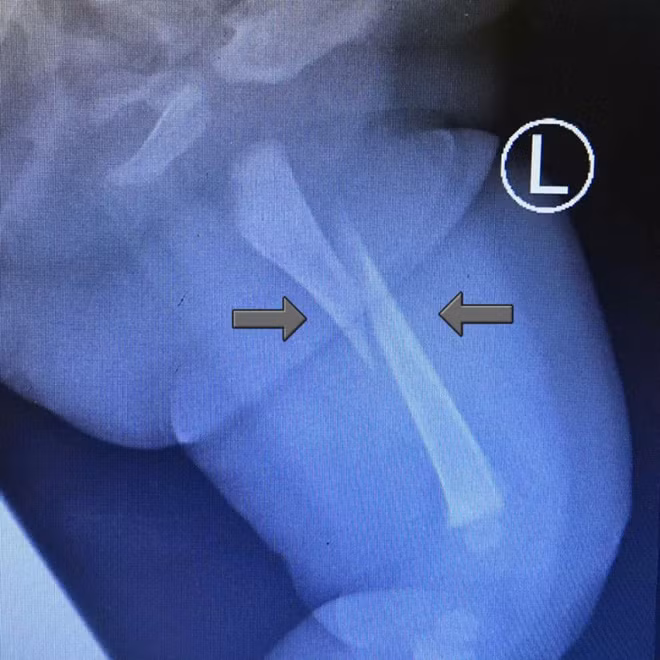

Là một phụ tá bác sĩ ở bệnh viện Shah Alam, bang Selangor, anh đã quyết định đưa con đi khám xem sao. Tại đây, người cha đã sốc khi nhìn kết quả X-quang cho thấy con mình bị gãy xương đùi.

Bác sĩ kết luận em bé bị gãy xương đùi.

Ảnh chụp X-quang cho thấy bé 3 tháng tuổi bị gãy xương đùi.